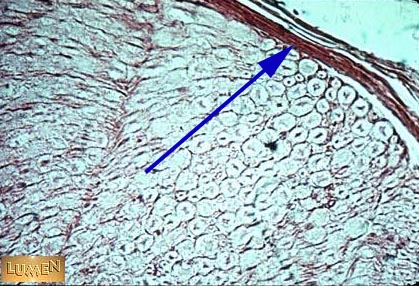

Q1 What is this tissue?

Q2 Name the layer of connective tissue that the arrow is indicating.

Peripheral nerve bundle.

Perineurium